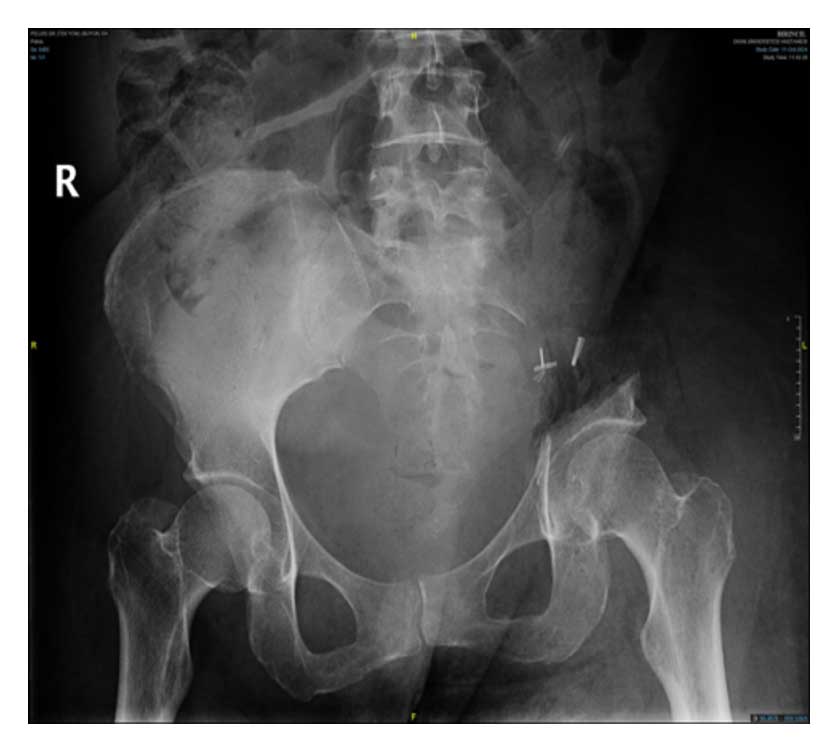

Ameliyat öncesi: Röntgende sol üreterde katater dışında anlamlı görüntü yok iken MR’da sol sakroiliak eklem seviyesinde düzensiz sınırlı içinde gaz gölgesi olan ve mesaneyi iten büyük yumuşak doku kitlesi görülmekte.

Ameliyat Sonrası: Röntgende sol sakroiliak rezeksiyon görülmekte.